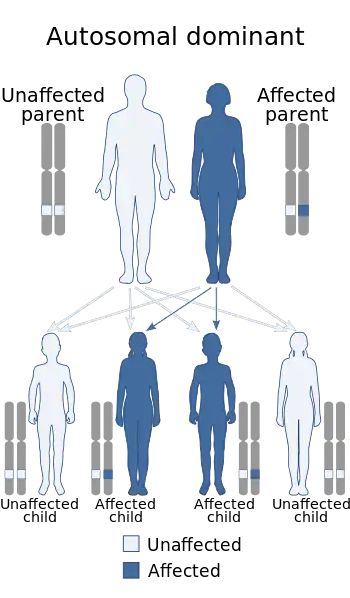

Tricho–dento–osseous syndrome (TDO) is a rare, systemic, autosomal dominant genetic disorder that causes defects in hair, teeth, and bones respectively. This disease is present at birth. TDO has been shown to occur in areas of close geographic proximity and within families; most recent documented cases are in Virginia, Tennessee, and North Carolina. The cause of this disease is a mutation in the DLX3 (distal-less 3) gene, which controls hair follicle differentiation and induction of bone formation. One-hundred percent of patients with TDO suffer from two co-existing conditions called enamel hypoplasia and taurodontism in which the abnormal growth patterns of the teeth result in severe external and internal defects.[1] The hair defects are characterized as being rough, course, with profuse shedding. Hair is curly and kinky at infancy but later straightens. Dental defects are characterized by dark-yellow/brownish colored teeth, thin and/or possibly pitted enamel, that is malformed. The teeth can also look normal in color, but also have a physical impression of extreme fragility and thinness in appearance. Additionally, severe underbites where the top and bottom teeth fail to correctly align may be present; it is common for the affected individual to have a larger, more pronounced lower jaw and longer bones. The physical deformities that TDO causes become more noticeable with age, and emotional support for the family as well as the affected individual is frequently recommended. Adequate treatment for TDO is a team based approach, mostly involving physical therapists, dentists, and oromaxillofacial surgeons. Genetic counseling is also recommended.

Cause

A single copy of the abnormal gene from one parent is able to cause the disease; this is called autosomal dominance. A mutation in the DLX3 gene has been confirmed as the cause of TDO. The onset of TDO begins with a 4 base pair deletion on chromosome 17q21, causing a mutation, specifically frameshift, and the termination codon to be the cause of the lack of complete maturation of the tooth enamel; this mutation is also responsible for the osseous defects in the bone. DLX-3 is expressed in the placenta and is significantly important during embryonic development in regards to hard bone tissue which is present in the teeth, skull, and long bones such as in the arms and legs. During normal tooth development, DLX 3 shifts from predominant expression in the inner enamel epithelium; the outer layer does not express DLX 3. In TDO cases, the DLX-3 is present on the outer enamel epithelium and leads to the dental abnormalities seen in this disease. Improper expression of DLX-3 causes the tooth enamel to be thinner, which leads to attrition and is most often the cause of dental abscess seen in TDO persons.

During osseous, connective tissue, and dermal cell differentiation, DLX 3 in TDO is also responsible for upper cranial thickness, calvaria, osteosclerosis of the long bones, long narrow head (dolichocephaly), abnormally thin brittle nails, and premature closing of fibrous joints. Consequently, 95% of people with TDO that are 16 years old or younger show skeletal abnormalities before full maturation takes place.[1] Lack of mastoid pneumatization by mastoid cells occurs in 82% of the cases and is rarely prevalent outside of TDO diagnosis.[1] Mastoid pneumatization occurs at about 6 months of ages and acts to minimize pressure fluctuations in the Eustachian tubes of the ear. The mastoid lies posterior to the lower jawbone (mandible) and distal to the ear. The Eustachian tube connects the middle ear to the back of the nose, and acts to create a specific pressure in the ear canal that causes vibrations to the eardrum; if adequate pressure is not attained, muffled, dull hearing results. In addition to the mastoid pneumatization assisting the Eustachian tubes for normal hearing, lack of mastoid pneumatization causes inflammation of the ear, general irritation, and does not allow enough air in to assist with mucus flowing out. It is not completely understood why gene mutations occur, but it is known that genetic mutations that cause disease are acquired from either or both parents at fertilization.[4]